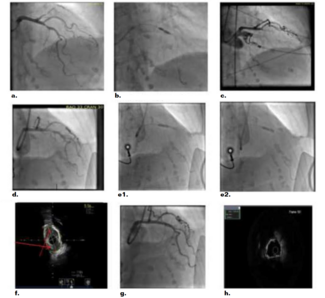

Toufik Mahfood Haddad, MD; Ann E. Narmi, MD; Nicolas W. Shammas, MD, MS, FACC, FSCAI, FACP, FSVM; Qais Radaideh, MD, MS; Nagarjuna Gujjula, MD

The effectiveness of coronary lithotripsy as a bailout approach.

Performing TAVR on a 73-year-old man with a EuroSCORE II of 12%.